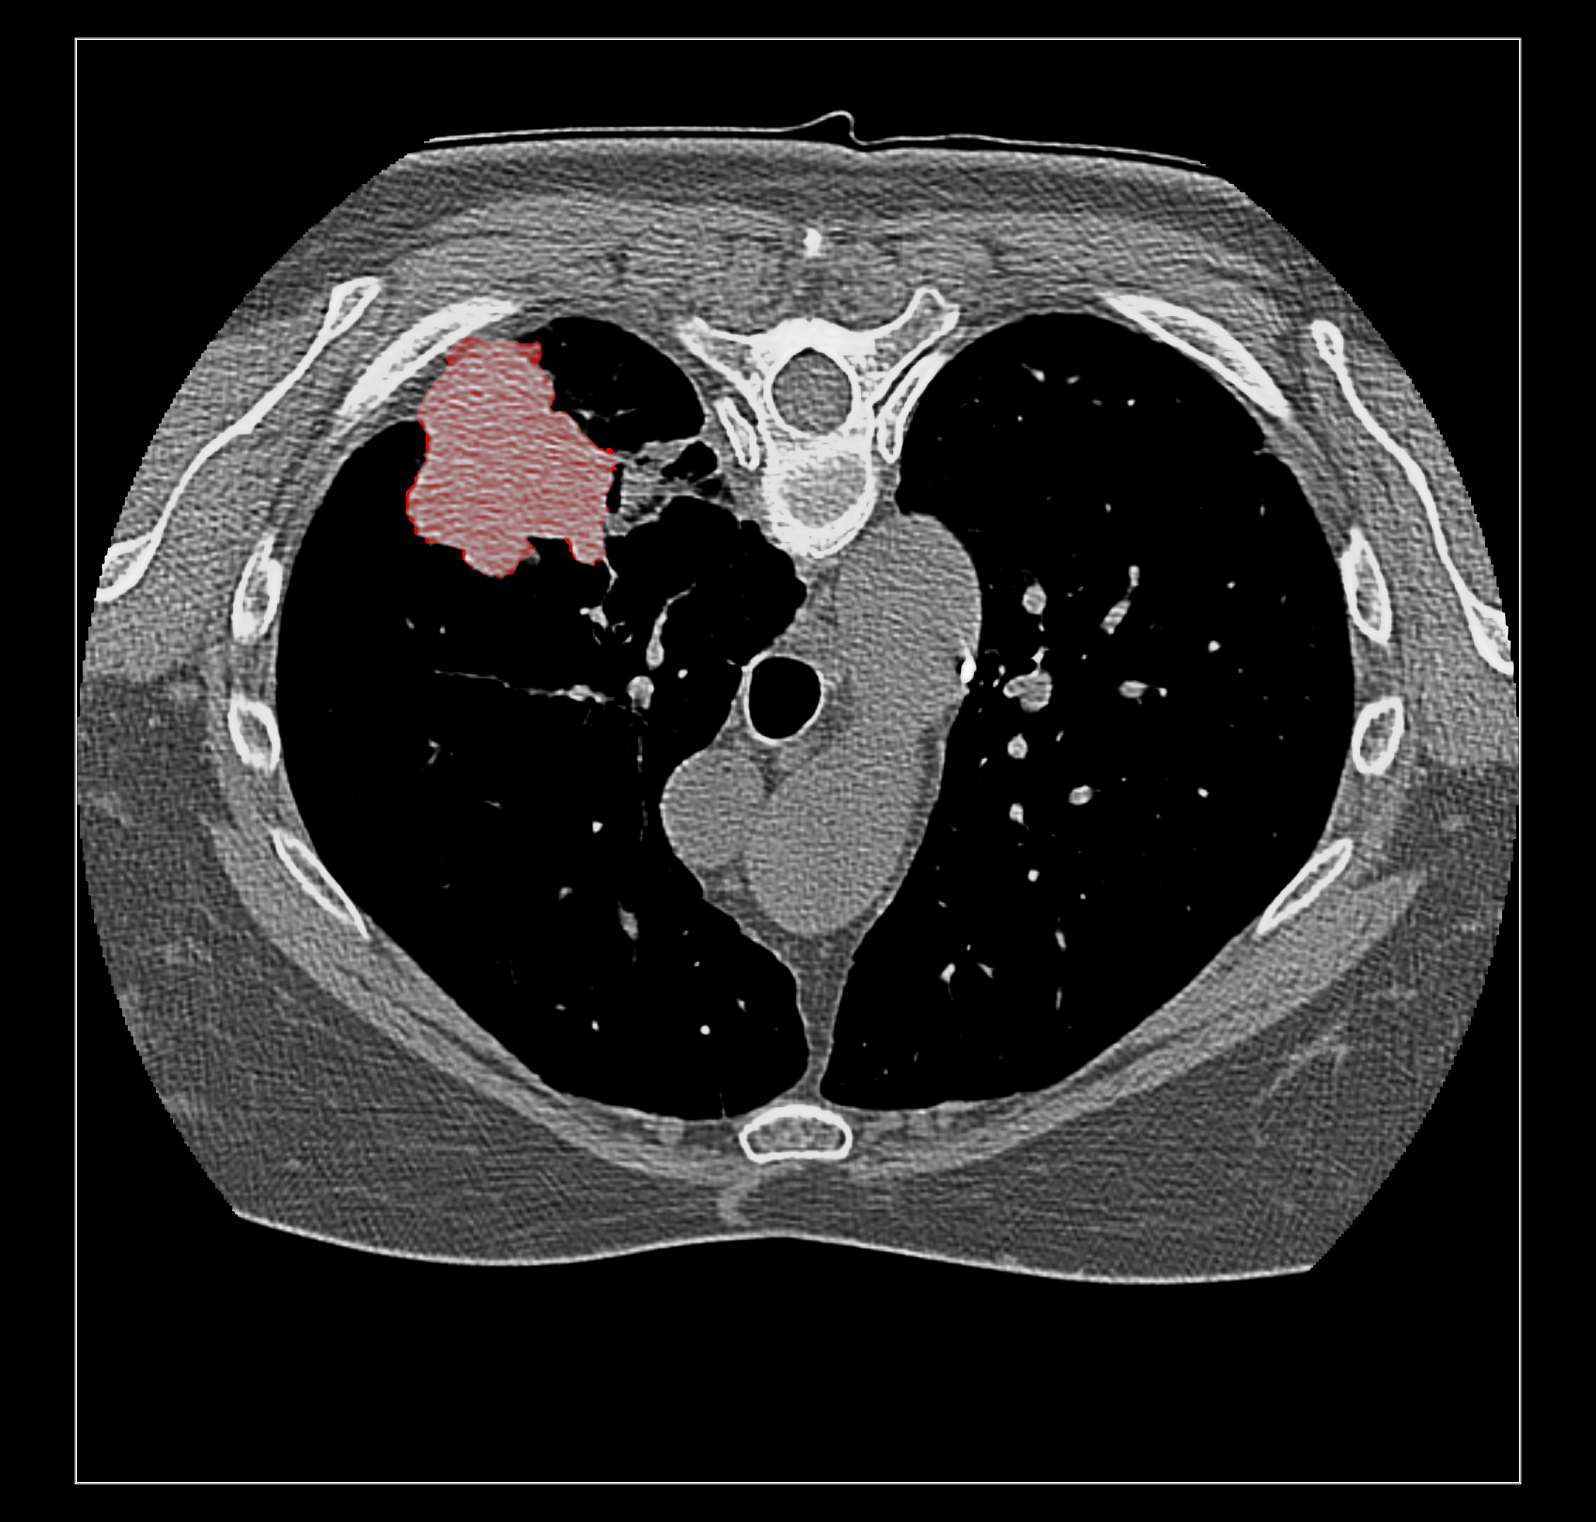

Surface rendering of segmentation channels avoids this problem. But I suspect coloring the image data according to the segmentation is far more useful to researchers looking at medical imaging because unlike a surface it allows you to see the intensities in the segmented region. For instance that helps you judge if the segmentation is correct. Sometimes a surface is best, for instance if you just want to see the size of a segmented tumor or compare the size a month ago to now using transparent surfaces can do that. I guess my overall assessment is that good quality medical imaging visualization needs the fancier blending. Because medical imaging is significantly different from electron and light microscopy there will be different needs that may be hard to implement like this blending problem. The priority of such time consuming improvements needs to be guided by medical imaging users.

Surface rendering of a segmentation with image rendering of a CT scan can look ok, and only the outline of the surface can be shown using volume command "capFaces false". Showing both segmentation and CT as image also works fine if the brightness curve is not narrow. I've attached images for all 3 styles made with

volume #1.1.1.1.2 style surface capFaces false

The capped surface flickers badly when rotating because the surface cap is at exactly the same depth as the image plane so a rendering depth fight ensues.

The surface outline is so thin on a retina display it is hard to see. Currently we don't support thicker lines because thick line support was dropped in modern OpenGL.

The surface style with plane CT image display adjusts when the plane is moved with the slider since the CT and segmentations are grouped as multichannel volume data.